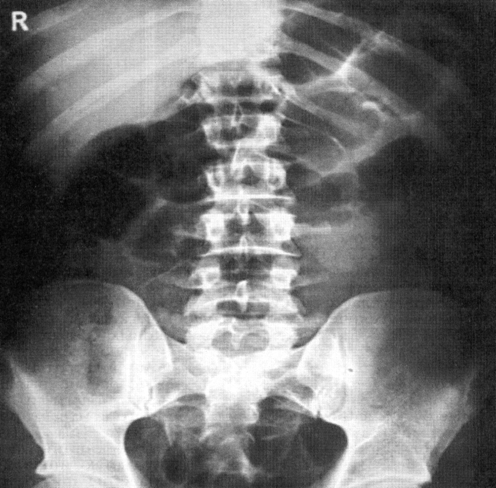

Рентген брюшной полости

5. В 21 примерно новые капельницы уже со спазмолитиками и следом клизма. Один оформленный кусочек стула. Рентген с барием в 22 часа. Вывод врача - немного все двигается, но ооочень медленно. Я отмечаю, что боли уже ниже по животу переместились. По моему личному выводу - движение есть. Врач не отвечает мне, что за большое черное пятно, которое я приняла за почку. Нервничает, так как сейчас ему следует решить оперировать или еще дать шанс. Я очень не хочу операцию. Я готова все сделать, чтобы ее не было, я об этом говорю. И врач решает сделать последний рентген с барием в 4 утра. Сказал еще ходить по лестницам.

2. В больнице проходят обязательные анализы: общий анализ крови и мочи для выявления воспалений, рентген для понимания есть ли признаки непроходимости, обязательный опрос хирургом и пальпация живота. Также проходят ЭКГ уже в качестве подготовки к операции. У меня еще было УЗИ для понимания есть ли перистальтика кишечника и выявления застоя газов в животе. Так то я ожидала что будут прослушивать перистальтику с помощью стетоскопа, но этого не было.

3. Для подтверждения диагноза и отслеживание течения болезни ты выпиваешь барий - белую жидкость. И далее с разницей в 3-4 часа делают рентген, отслеживающий нахождение этой жидкости в брюшной полости. В идеале 6-8 часов с выходом бария вместе с каловыми массами.